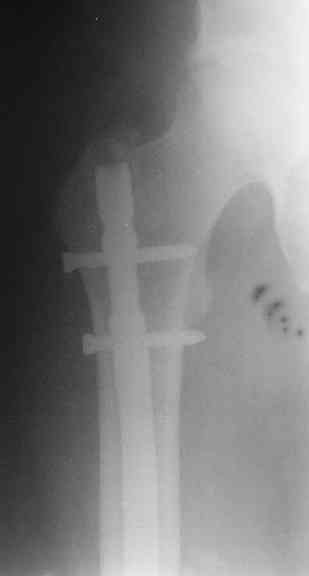

Вот несколько. С тисками и трубой на днях сделаем.

> Вот несколько. С тисками и трубой на днях сделаем.

Саша, последний штифт, пожалуй, перегнули?

> Саша, последний штифт, пожалуй перегнули?

Там заход сделан как для прямого штифта, не через вертел.